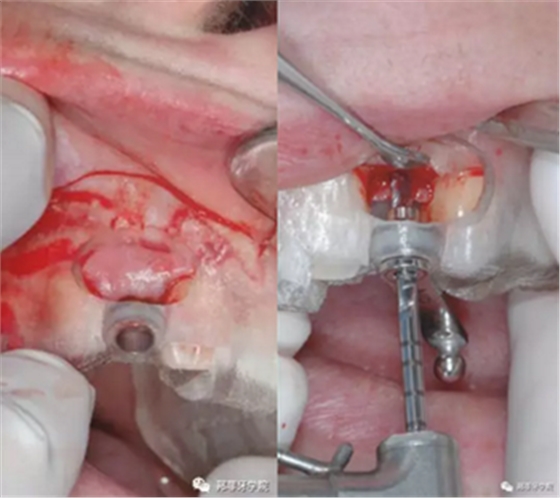

本病例中,缺隙足夠在保持天然牙與植體之間最小距離1.5mm的情況下兩側各植入1枚3.5mm Nobel Replace Tapered Groovy植體。手術導板設計頰側開窗,方便操作及固位。采用嵴頂切口,翻粘骨膜瓣(圖5 & 6)。

圖5 & 6:手術導板頰側開窗設計

采用手術導板進行備洞及植入,植入扭矩35Ncm。植體適當偏腭側植入,避免鄰近結構破壞及前庭處骨外壁穿孔。植體肩臺位于鄰牙釉牙本質界根尖方2mm(圖7&8)。

圖7 & 8:導板下備洞及植入